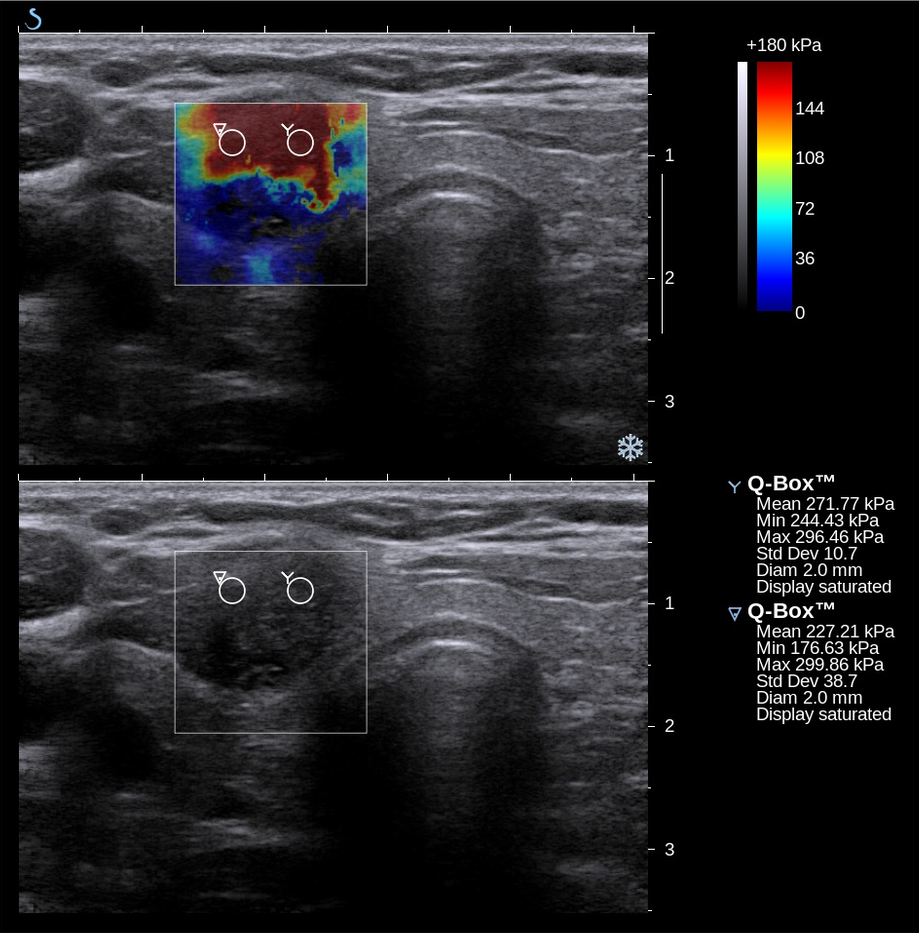

2. Ultrasound Elastography

Ultrasound elastography uses sound waves to "see" how tissue deforms under stress. Many researchers consider it the gold standard for stiffness measurement.

Its strength lies in depth and precision. Elastography can image both superficial and deep tissue layers, providing detailed, real-time maps of stiffness. Because of this, it is frequently used as a reference standard in clinical research.

It is important to note that elastography measures stiffness, not tension. Stiffness here means how quickly mechanical waves travel through the tissue, which reflects its material properties at rest.

This is different from tension, which refers to how much a muscle resists when you press into it. The two are related, but not interchangeable.

The other limitation is accessibility. Machines cost $20,000 or more and require specialized training to operate. For most therapists, it is not practical to use in daily sessions.